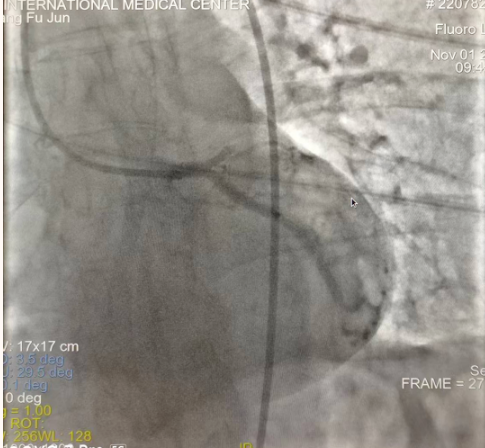

閉塞的血管再通時(shí)間取決于急救時(shí)長(zhǎng)、轉(zhuǎn)運(yùn)時(shí)長(zhǎng)和治療時(shí)長(zhǎng),在前兩方面,醫(yī)院已為患者爭(zhēng)取了最短時(shí)間?;颊呒覍龠h(yuǎn)在陜北,雖然已在趕來的路上,但最快抵達(dá)西安也要3小時(shí),在與患者家屬電話溝通同意急診手術(shù)后,醫(yī)療總值班代家屬簽字,康曉軍在請(qǐng)示心臟病醫(yī)院王海昌院長(zhǎng)及心臟內(nèi)科CCU尚福軍主任后,積極進(jìn)行術(shù)前準(zhǔn)備。在沒有家屬陪同、沒有交費(fèi)、沒有辦入院手續(xù)的情況下,患者經(jīng)胸痛中心綠色通道被送往心臟冠脈介入手術(shù)室,打通了完全閉塞的心臟前降支近段血管。